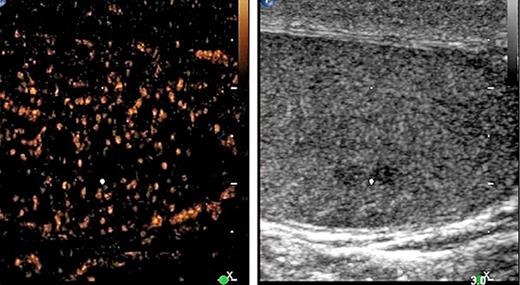

1st patient: this 43-year-old man presented with left-sided testicular discomfort. Contrast-enhanced scrotal ultrasonography demonstrated unspecific irregularities of the intratesticular echo pattern (Fig. 1). Scrotal MRI was likewise inconclusive. The classical serum tumour markers were all in the normal range. Therefore, the patient was put on a surveillance schedule. As the patient moved to another city, he was lost to follow-up. But, enquiries disclosed that orchiectomy for classical seminoma (pT1, clinical stage [CS] 1) was performed on him at another institution 4 months after our primary assessment. The serum level of miR371a-3p at the time of primary examination was RQ = 39.45 which is much higher than the normal range. Knowledge about the elevated miR-level would clearly have changed decision-making. No follow-up measurements of miR371a-p were available.

B-mode (right side of figure) and contrast-enhanced ultrasonographic (CEUS, left side) images of left testis of patient #1. The white dot denotes a small hypo-echoic lesion suspicious of neoplasia in the B-mode scan. However, CEUS does not reveal any enhancement of air bubbles in the corresponding region, and thus the presence of a testicular tumour was excluded.